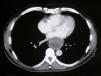

Presentamos el caso de un varón de 53 años, con antecedentes personales de HTA y parálisis facial periférica derecha desde hacía 2 años. En el estudio de una posible miopatía se encontró en la radiología simple de tórax una masa mediastínica posterior, motivo por el cual fue remitido a nuestra consulta. Se completó el estudio con una TAC de tórax que confirmó la masa de 63 x 57mm, hipodensa, tabicada y localizada en el mediastino posterior (fig. 1). Provocaba compresión y desplazamiento de la luz del tercio inferior del esófago y de la pared posterior de la aurícula izquierda, compatible con un posible leiomioma esofágico. Se efectuó una toracotomía posterior izquierda, a través del 7.° espacio intercostal, encontrando una tumoración quística y encapsulada, localizada en el trayecto del nervio vago izquierdo. La lesión era extra esofágica y estaba recubierta por la pleura mediastínica paraesofágica. Se resecó completamente tras ligar los pedículos vasculares y liberar las adherencias sobre el esófago. El informe histopatológico reveló un tumor quístico de 65 x 58mm, unilocular, que presentaba el patrón clásico bifásico de alternancia de áreas de Antoni tipo A y tipo B de los schwannomas benignos. El postoperatorio transcurrió sin complicaciones, siendo dado de alta hospitalaria el tercer día tras la intervención.